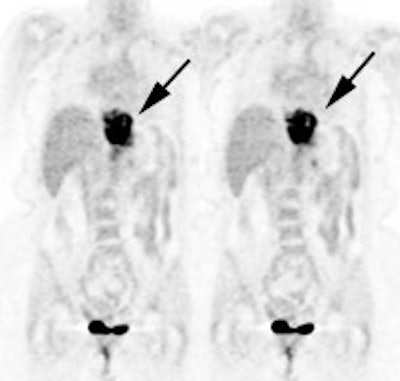

Unsuspected metastatic esophageal carcinoma: The patient shown in the case below was referred for FDG PET imaging for the evaluation of esophageal carcinoma. A CT scan demonstrated abnormal thickening of the distal esophagus (white arrow), but no evidence of metastatic disease. The PET exam revealed long segment abnormal increased tracer activity within the primary esophageal lesion, as well as an unsuspected bone metastasis to the right hip (black arrow). Such findings on PET imaging have tremendous impact on patient management. Case courtesy of CTI.